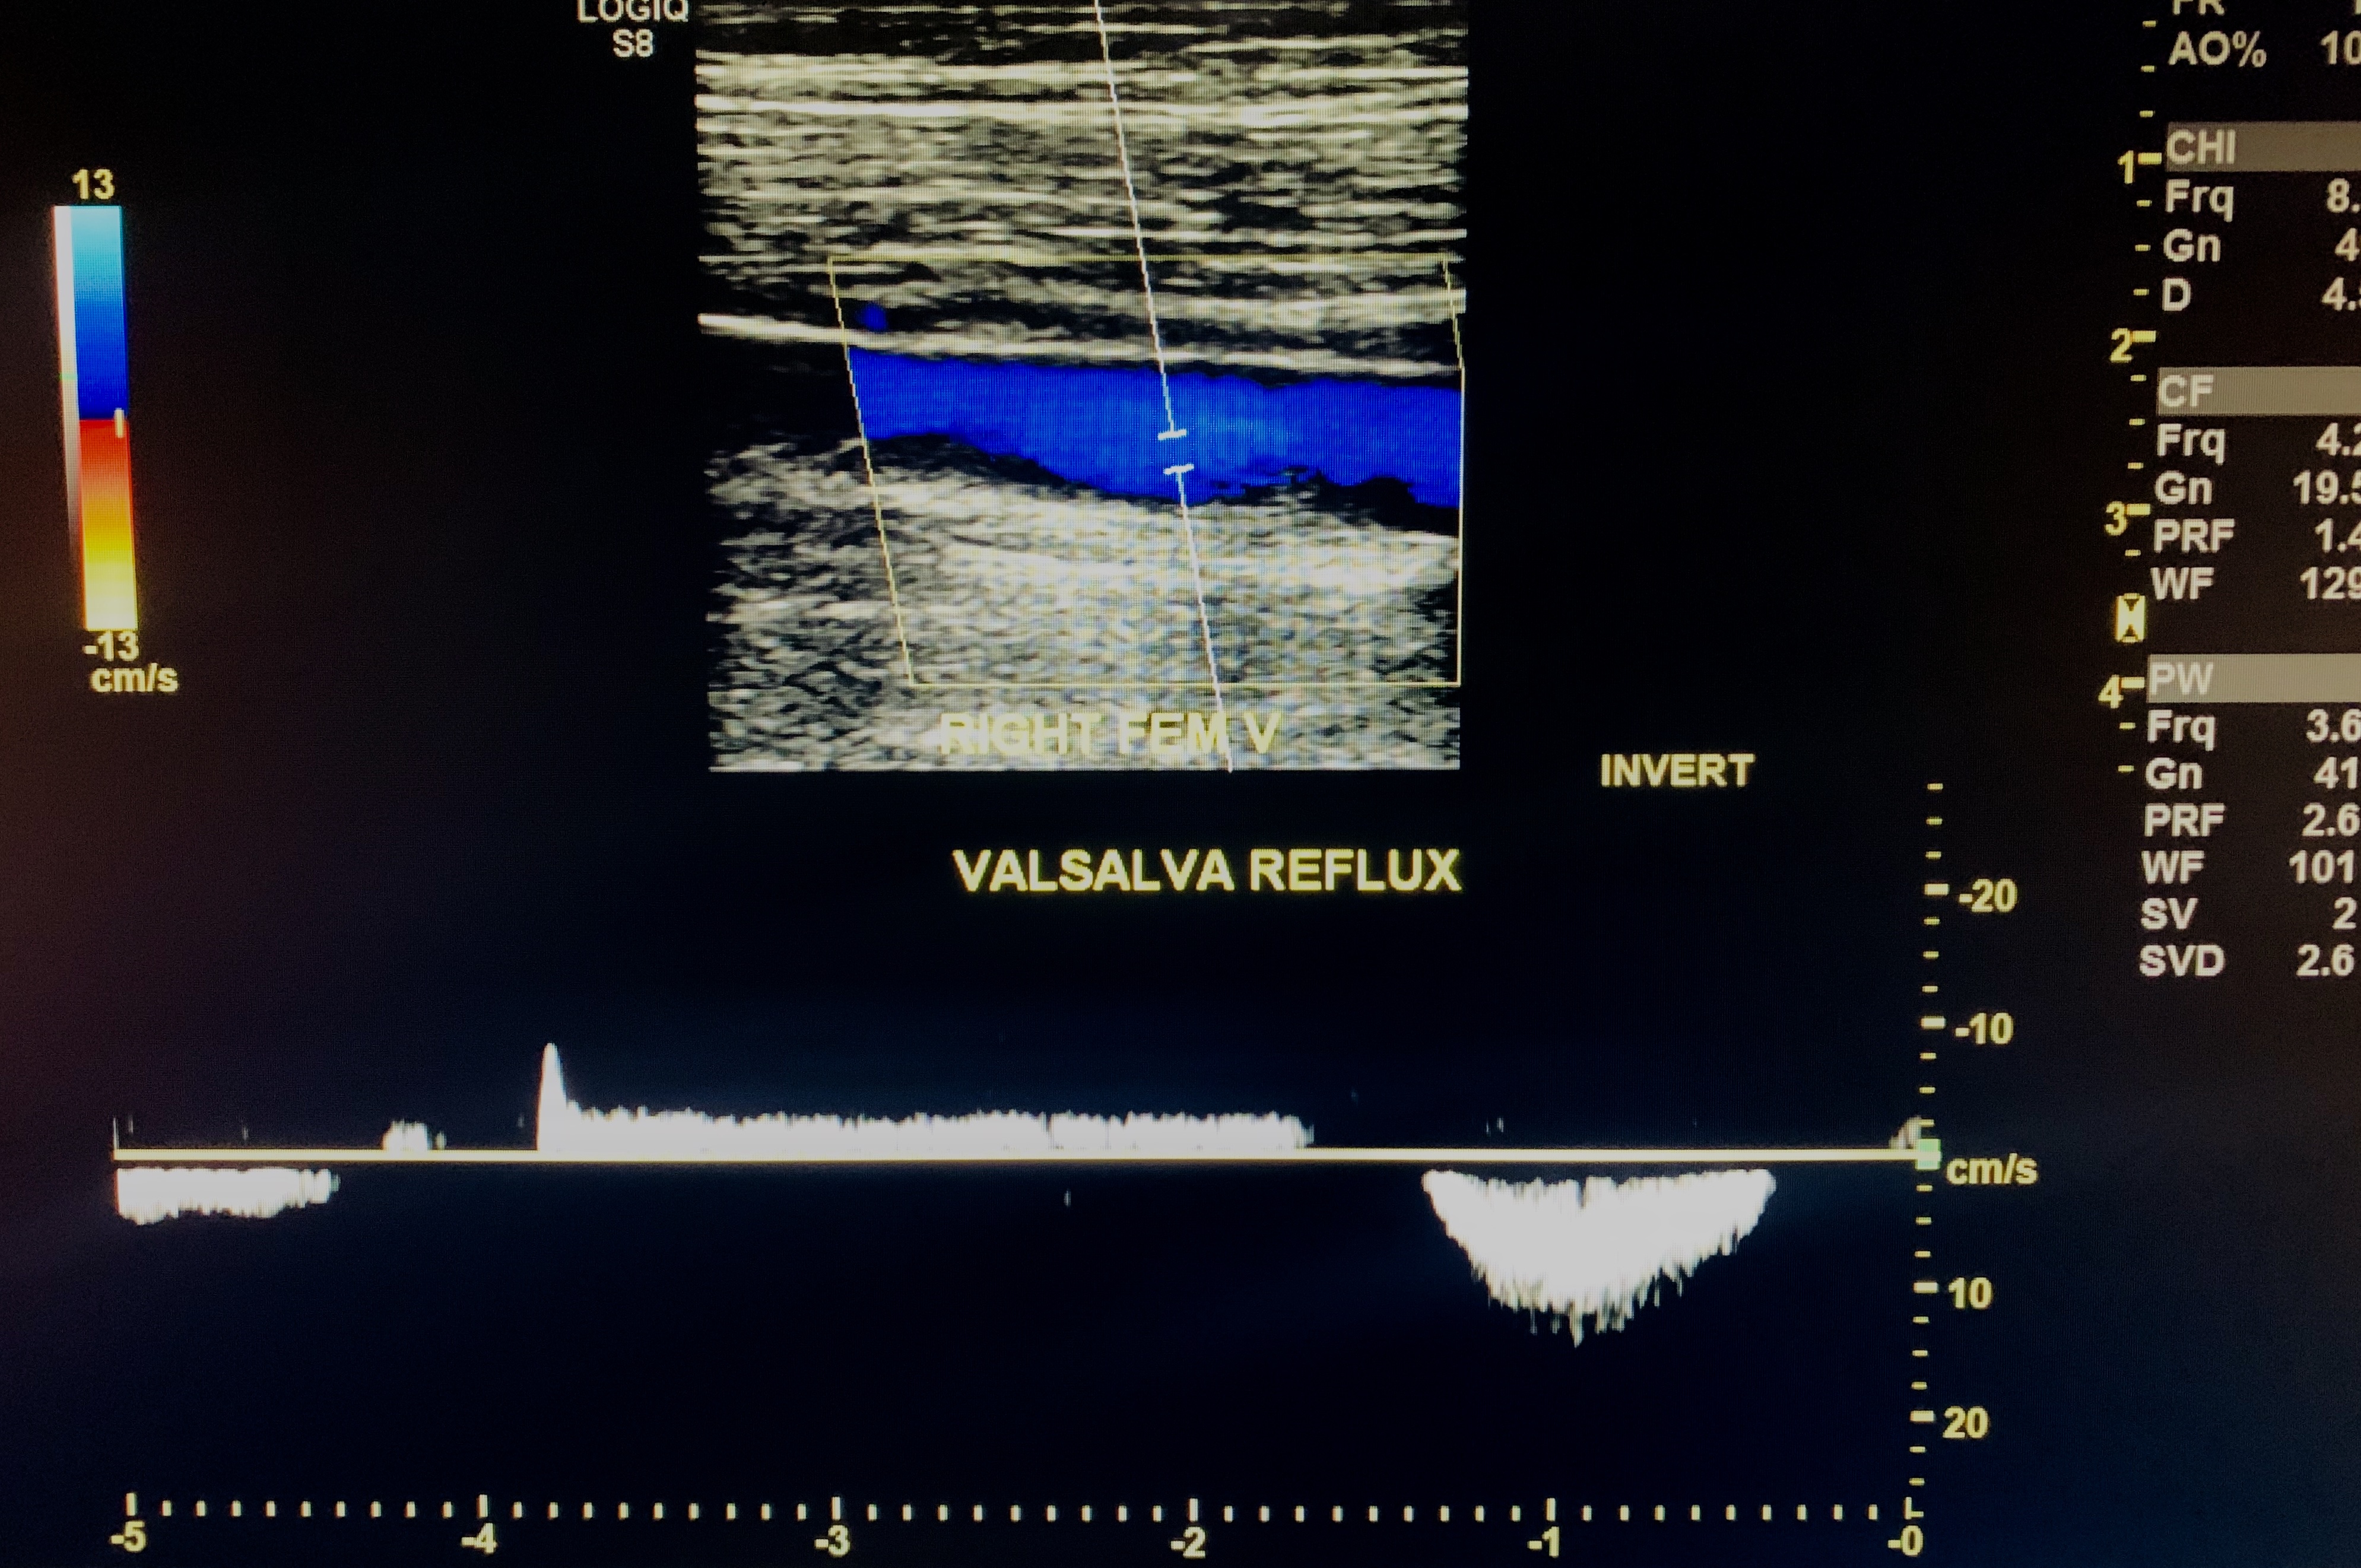

Check For Deep Vein Reflux

Reflux in the deep veins is considered spectral reversal >1 second. Venous reflux (Valvular incompetence) was then demonstrated in the CFV, the femoral vein, and

posterior tibial veins along with an incompetent perforator vein in the right leg.

Femoral vein reflux